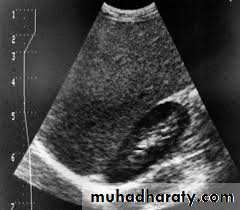

Normal renal ultrasound.

A longitudinal view of the right kidney was obtained by passing the sound beam through the right lobe of the liver. The kidney is seen behind this, outlined by the markers. The central bright echoes in the kidney are due to fat around the collecting system.